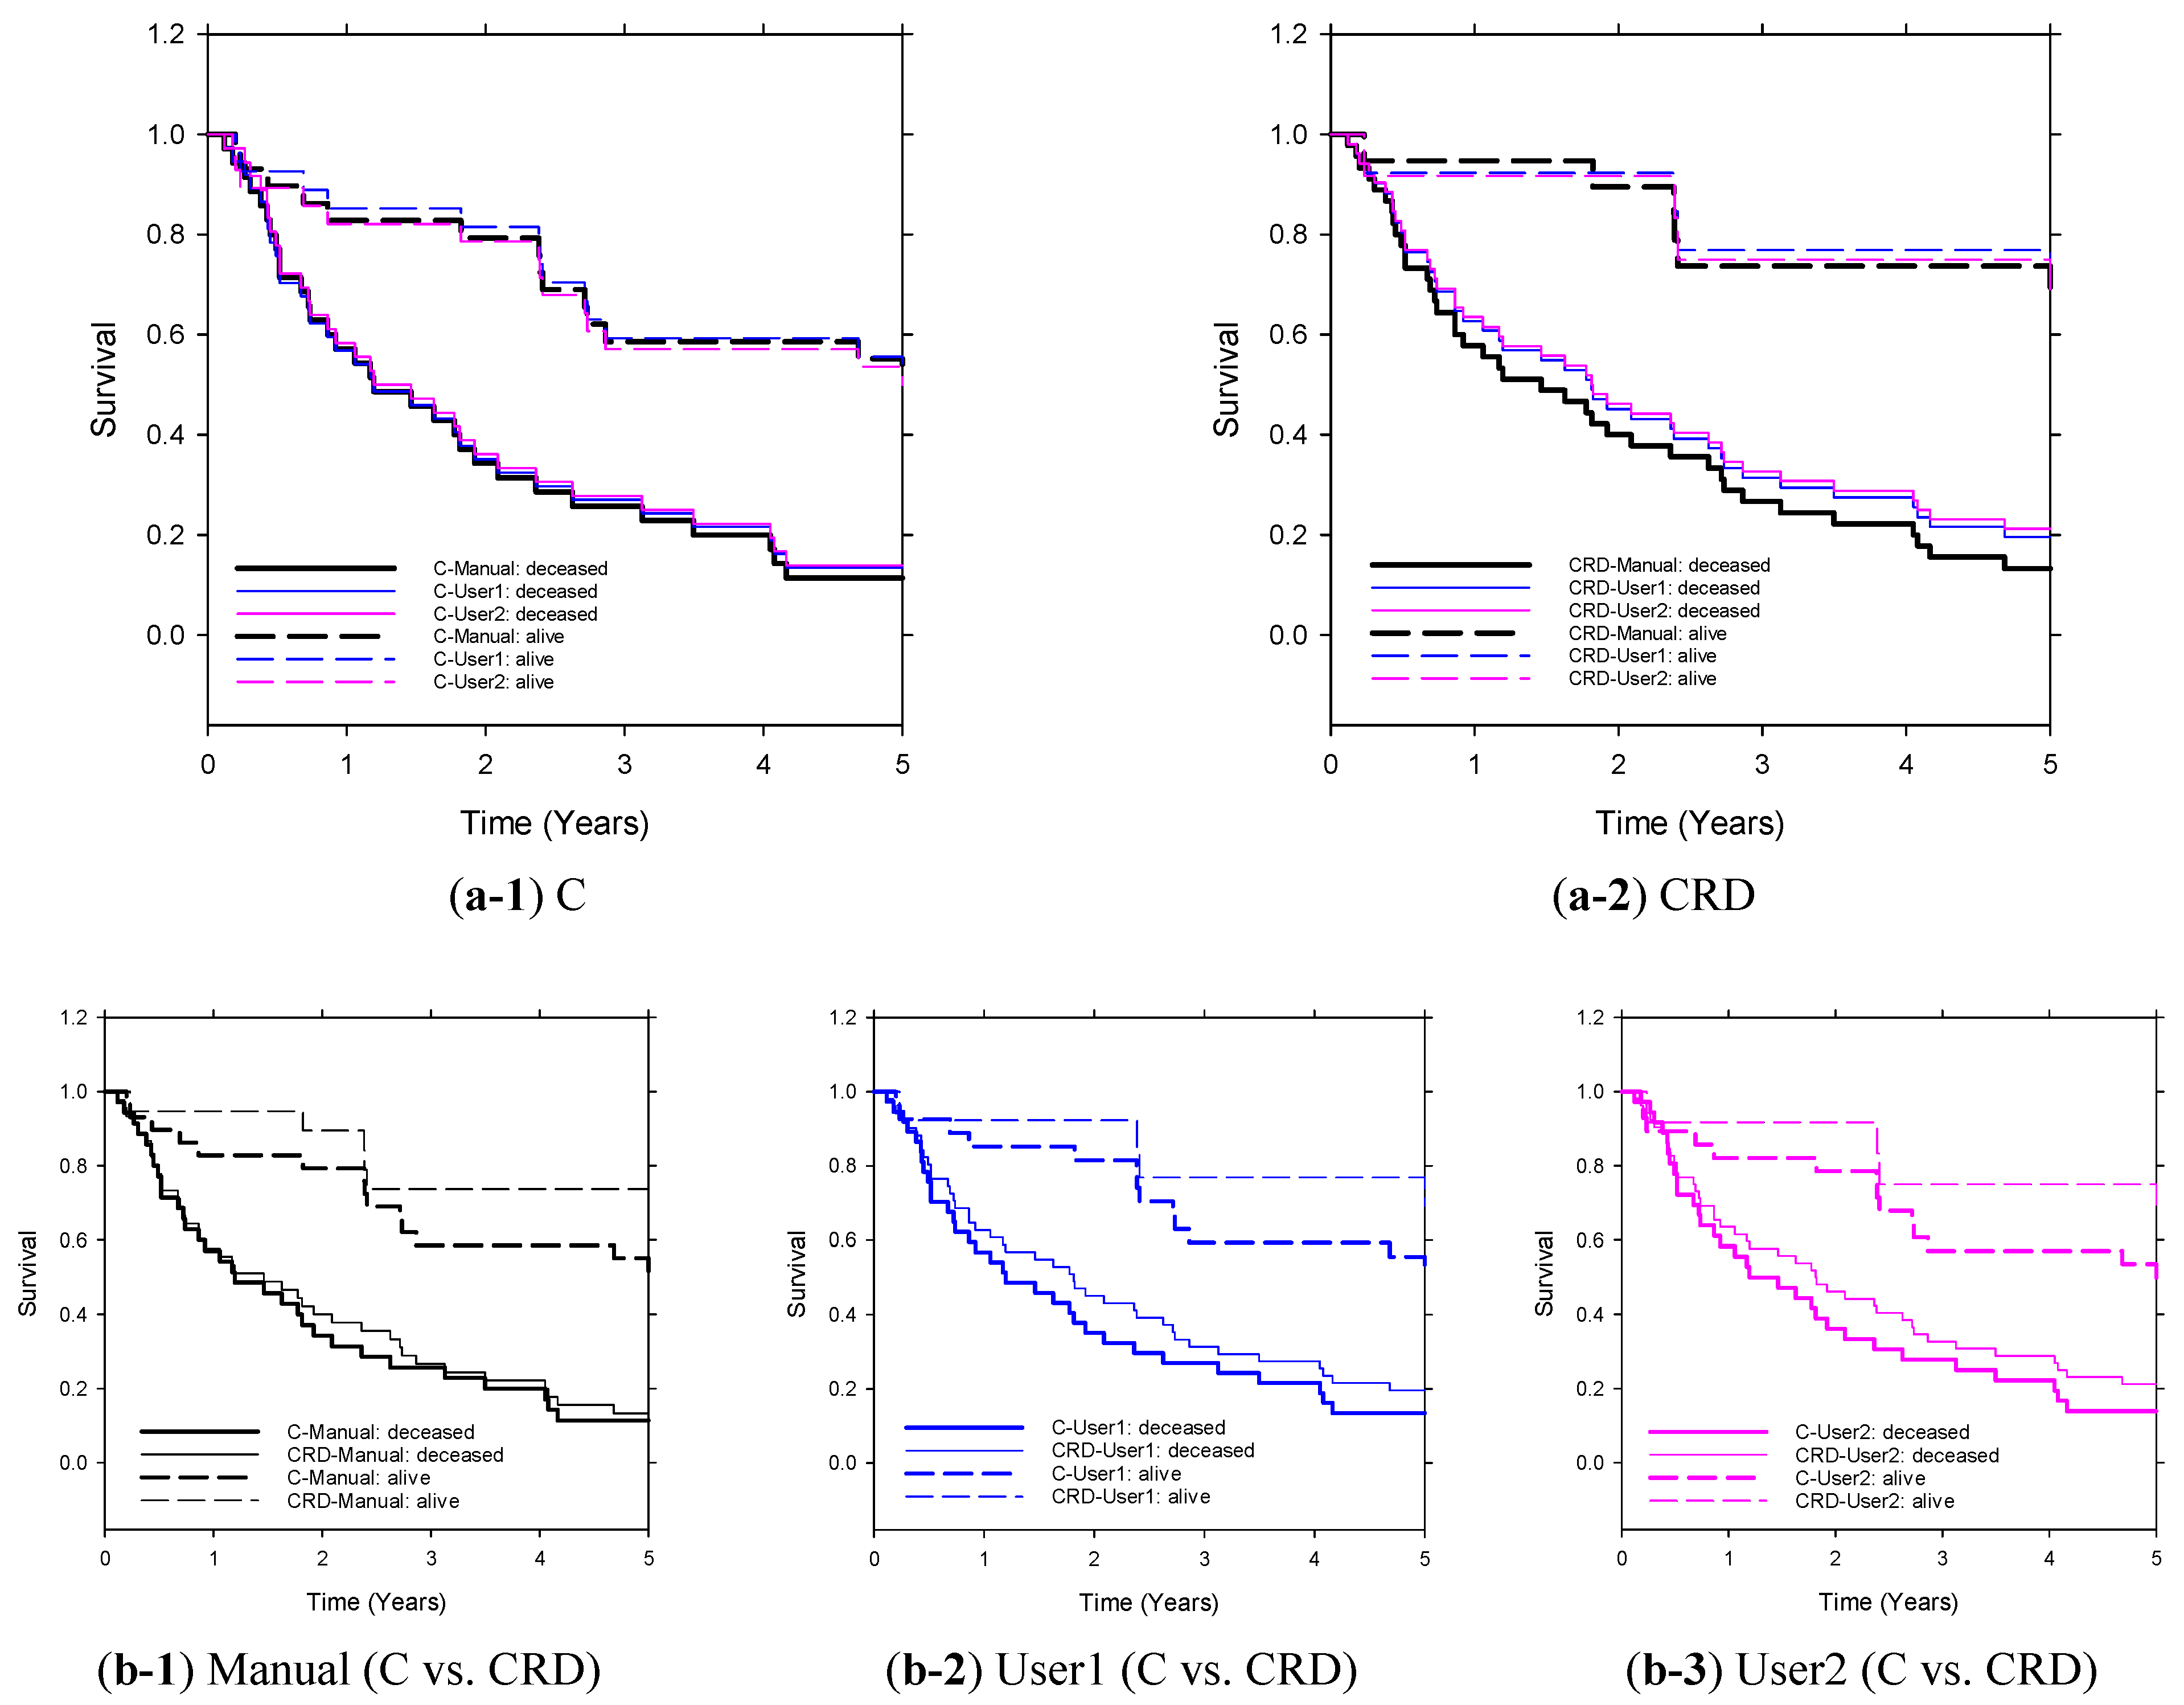

3.3. Five-Year Survival Prediction

3.4. LLM Direct Survival Prediction